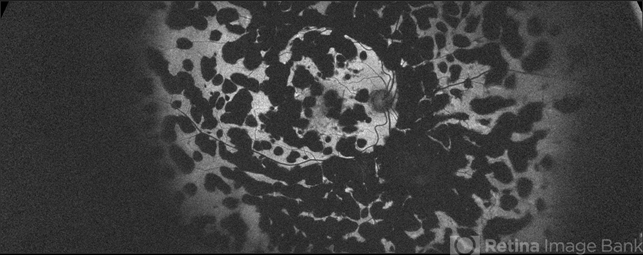

- End stage PDR with extensive Heavy Focal PRP Scars

- fundus autofluorescence (FAF), focal laser, proliferative diabetic retinopathy (PDR)

- 65-year-old, African American, woman with inactive PDR, S/P multiple PRP/ heavy focal OU, now receiving simultaneous Ozurdex/ Eylea injection OS, on regular basis w/ long standing poor vision 20/200-20/400 OS, since 2016 - patient was and currently being treated by another physician.